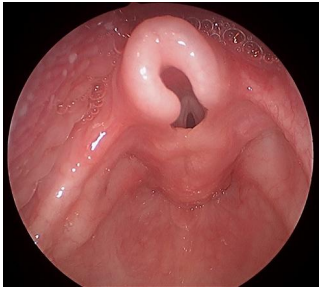

Mulher, 56 anos de idade, tabagista há 25 anos, refere rouquidão progressiva nos últimos 6 meses, associada à voz soprosa e fadiga vocal, além de dispneia aos esforços moderados. Nega disfagia ou perda ponderal. Nega história de trauma laríngeo. Ao exame, encontra-se eupneica em repouso. A avaliação vocal demonstra voz rouca, grave e soprosa. A videolaringoscopia em abdução mostra os achados apresentados na imagem a seguir:

Enunciado 4540959-1

Além de medidas antitabagismo, qual é a melhor conduta terapêutica?